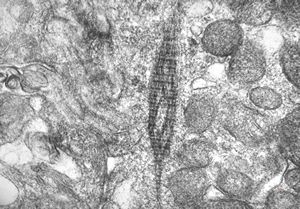

F,49y. | normal kinocilium - bronchus